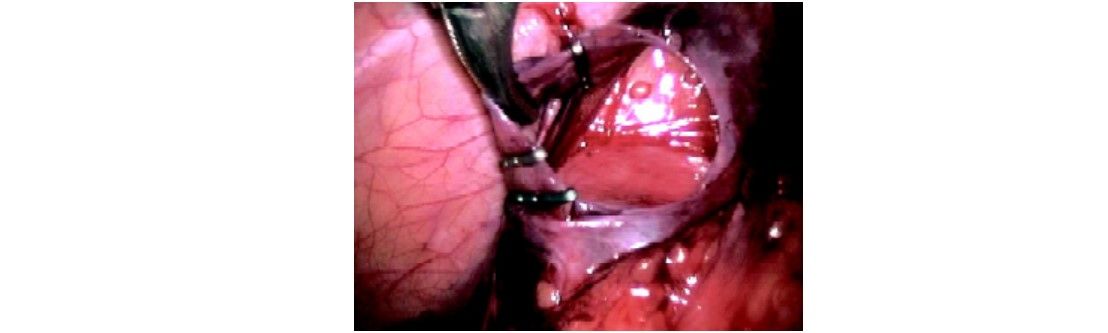

Endoscopic clip applier is used to secure it or intracorporeal suturing is used to ligate the gonadal vein or veins while sparing the artery.

Clips applied around a spermatic vein